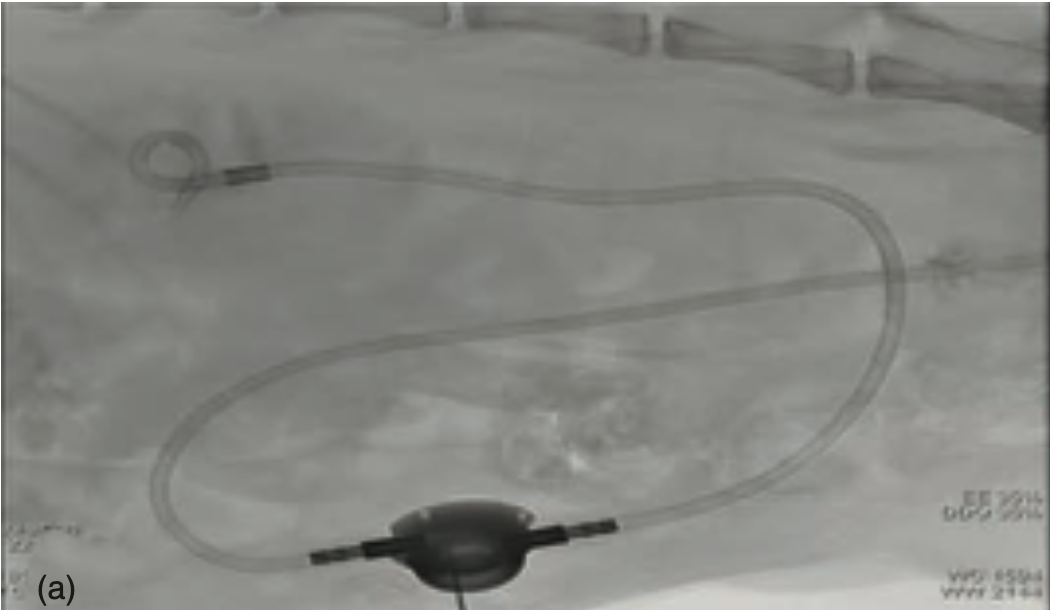

БСйчас всё Ρ‡Π°Ρ‰Π΅ ΠΈΡΠΏΠΎΠ»ΡŒΠ·ΡƒΡŽΡ‚ минимально ΠΈΠ½Π²Π°Π·ΠΈΠ²Π½Ρ‹Π΅ ΠΌΠ΅Ρ‚ΠΎΠ΄Ρ‹ , Π½Π°ΠΏΡ€ΠΈΠΌΠ΅Ρ€:

1. Установка ΠΌΠΎΡ‡Π΅Ρ‚ΠΎΡ‡Π½ΠΈΠΊΠΎΠ²ΠΎΠ³ΠΎ стСнта

Вонкая Ρ‚Ρ€ΡƒΠ±ΠΎΡ‡ΠΊΠ°, ΠΊΠΎΡ‚ΠΎΡ€ΡƒΡŽ вводят Π²Π½ΡƒΡ‚Ρ€ΡŒ ΠΌΠΎΡ‡Π΅Ρ‚ΠΎΡ‡Π½ΠΈΠΊΠ°. Она ΠΏΠΎΠΌΠΎΠ³Π°Π΅Ρ‚ ΠΌΠΎΡ‡Π΅ свободно ΠΏΡ€ΠΎΡ…ΠΎΠ΄ΠΈΡ‚ΡŒ, Π΄Π°ΠΆΠ΅ Ссли Π΅ΡΡ‚ΡŒ ΠΊΠ°ΠΌΠ½ΠΈ ΠΈΠ»ΠΈ Ρ€ΡƒΠ±Ρ†Ρ‹.

2. SUB-устройство (ΠΏΠΎΠ΄ΠΊΠΎΠΆΠ½Ρ‹ΠΉ ΡˆΡƒΠ½Ρ‚)

Π‘ΠΏΠ΅Ρ†ΠΈΠ°Π»ΡŒΠ½ΠΎΠ΅ устройство, ΠΊΠΎΡ‚ΠΎΡ€ΠΎΠ΅ ΠΏΠΎΠ΄ΠΊΠ»ΡŽΡ‡Π°ΡŽΡ‚ ΠΌΠ΅ΠΆΠ΄Ρƒ ΠΏΠΎΡ‡ΠΊΠΎΠΉ ΠΈ ΠΌΠΎΡ‡Π΅Π²Ρ‹ΠΌ ΠΏΡƒΠ·Ρ‹Ρ€Ρ‘ΠΌ. Π­Ρ‚ΠΎ Ρ€Π°Π±ΠΎΡ‚Π°Π΅Ρ‚ ΠΊΠ°ΠΊ Β«ΠΎΠ±Ρ…ΠΎΠ΄Π½ΠΎΠΉ ΠΏΡƒΡ‚ΡŒΒ» для ΠΌΠΎΡ‡ΠΈ, Ссли ΠΌΠΎΡ‡Π΅Ρ‚ΠΎΡ‡Π½ΠΈΠΊ Π·Π°Π±Π»ΠΎΠΊΠΈΡ€ΠΎΠ²Π°Π½, Ρ‡Π°Ρ‰Π΅ всСго Ρ‚Π°ΠΊΠΎΠ΅ происходит ΠΏΡ€ΠΈ скоплСнии большого количСства ΠΊΠ°ΠΌΠ½Π΅ΠΉ.